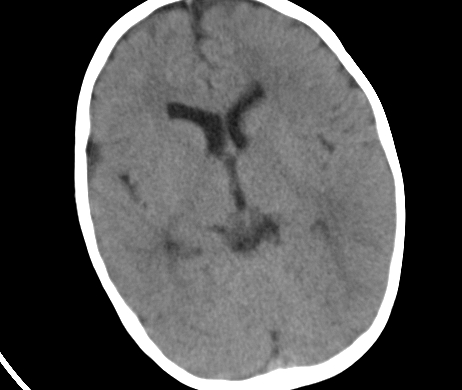

标题: PED1850:男 2岁 头部外伤1天,有事吗?

男 2岁 头部外伤1天,有事吗?科里意见不一 骨窗 没事,未上传

未见与外伤有关病变;脑白质的比例较少,有发育异常吗?